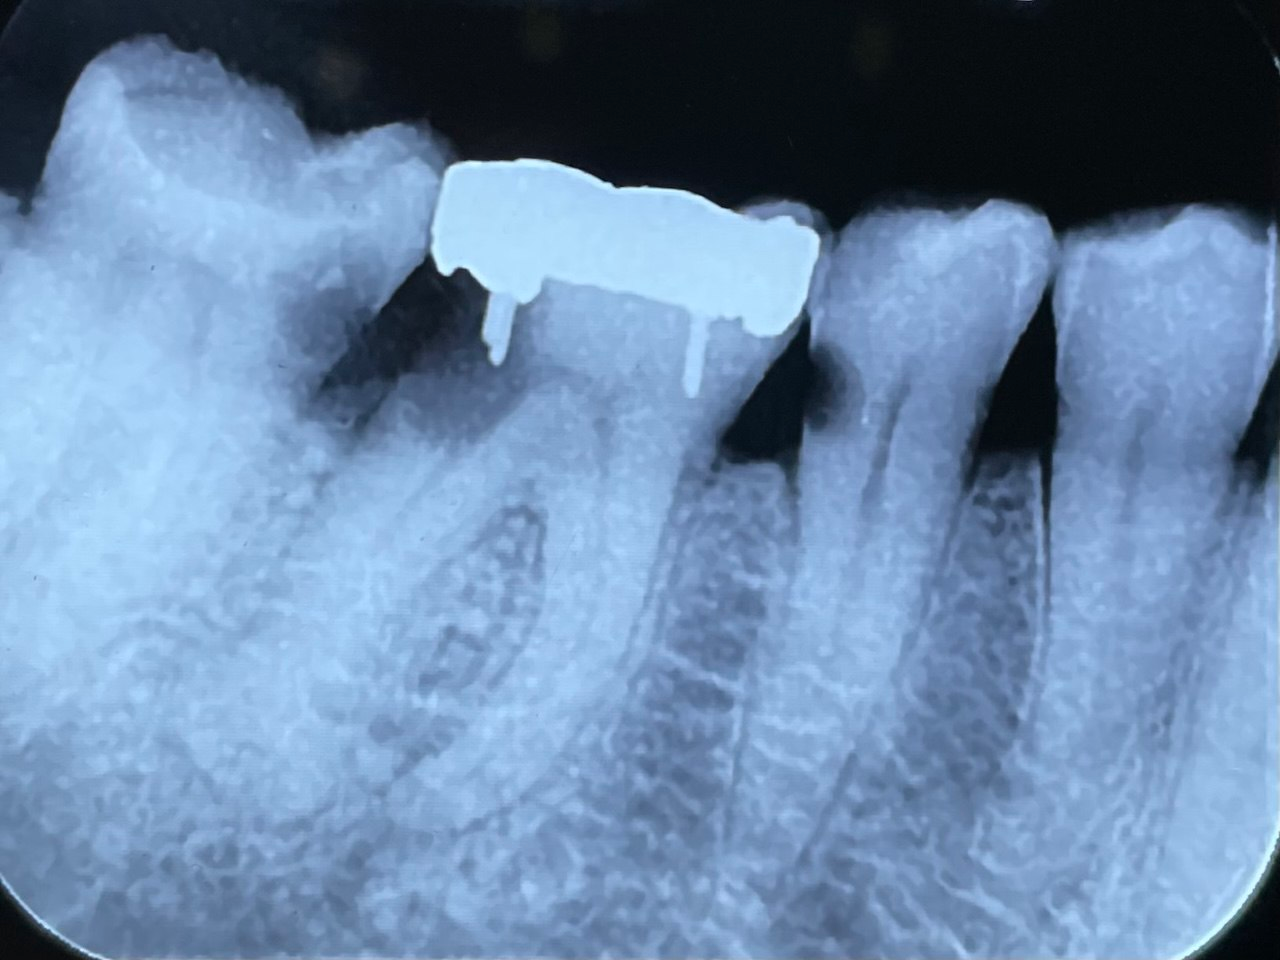

8. Which surface needs restoration?